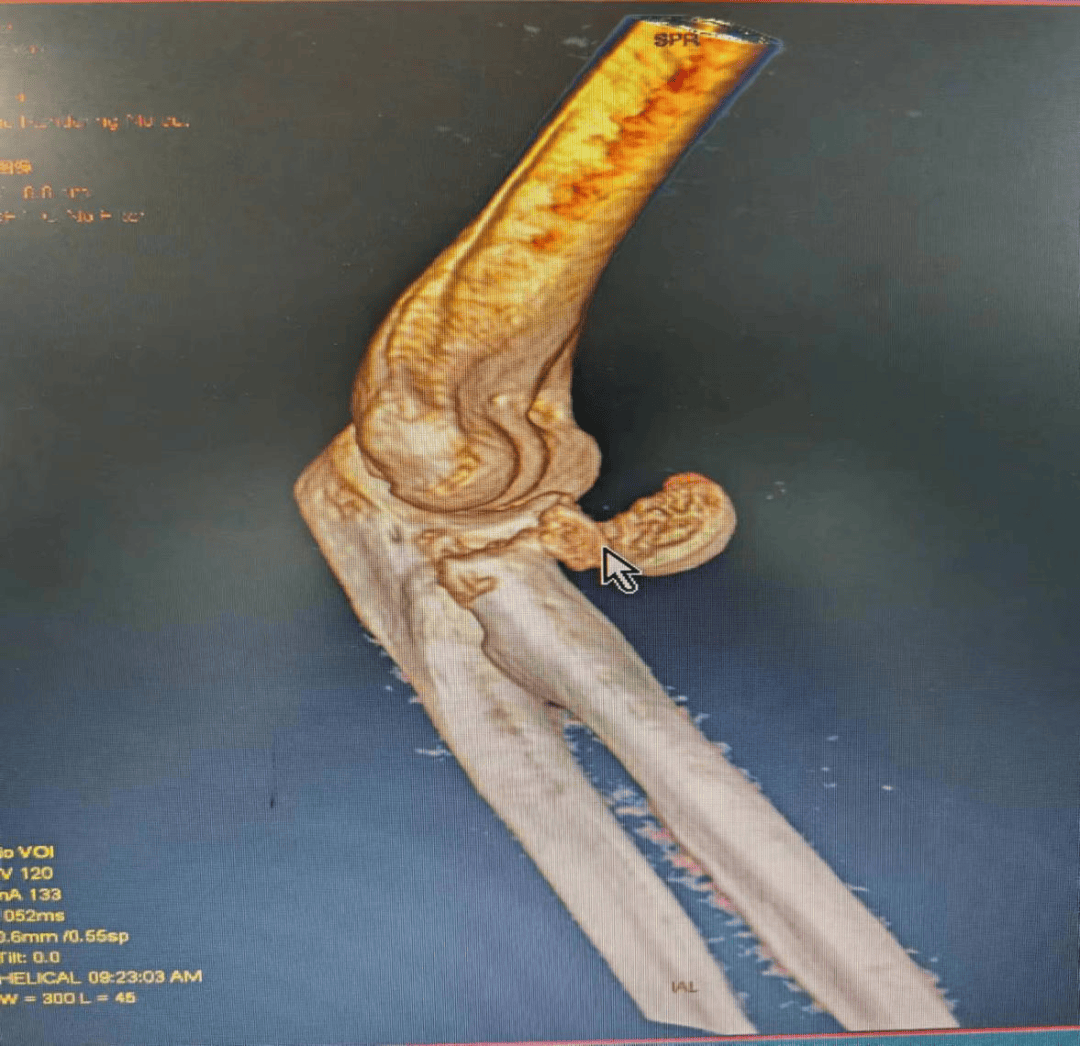

5月20日,48岁的胡女士在不慎摔倒,致右侧肘关节疼痛、活动受限。家属在当地医院行DR检查示:右侧桡骨头骨折,明显移位,入我院骨科西区住院治疗。骨科西区医生对其进行了详细的检查,根据检查结果诊为右侧桡骨头粉碎性骨折。

图为术前三维CT

骨科西区王医师第一时间为胡女士进行了手法复位及肘关节石膏固定和消肿对症治疗,以避免损伤加重。“此例桡骨头骨折为Mason分型III型,由于桡骨头粉碎程度太大,无法采用传统切开复位内固定方式,若采用桡骨小头切除术,病人因年龄较轻,后期会带来多种并发症,对患者的远期生活会带来严重的影响。术前与患者及家属沟通后,决定采用桡骨头置换术,使肘关节较快恢复到正常功能”王医师说。